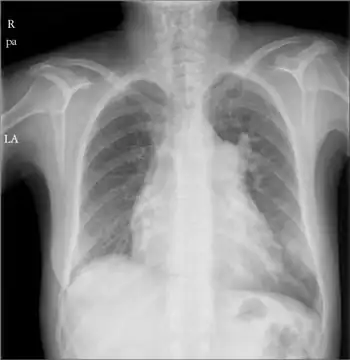

Right atrial enlargement

| Right atrial enlargement (P pulmonale) | |

Right atrial enlargement (RAE) is a form of cardiomegaly, or heart enlargement. It can broadly be classified as either right atrial hypertrophy (RAH), overgrowth, or dilation, like an expanding balloon. Common causes include pulmonary hypertension, which can be the primary defect leading to RAE, or pulmonary hypertension secondary to tricuspid stenosis; pulmonary stenosis or Tetralogy of Fallot i.e. congenital diseases; chronic lung disease, such as cor pulmonale. Other recognised causes are: right ventricular failure, tricuspid regurgitation, and atrial septal defect.[1]